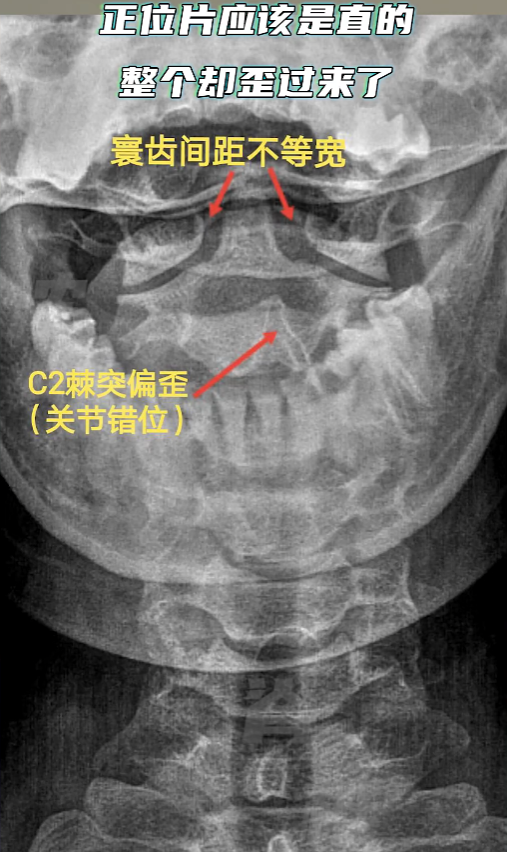

3、影像学检查

医生通常会要求患者至少进行症状区域节段的脊椎X光检查,如有必要则会建议进一步做MR或CT检查。许多患者总有类似的疑问:MR和CT不是看得更清楚吗?为什么不直接做这两项检查?其实不同的检查手段各有其适用情况。

对于医生而言,便宜、出片快、较低辐射量的X光已经足以检视骨关节的结构、排列和完整性,从而验证触诊检查时发现的脊椎错位情况以及排除手法禁忌症;如需排查椎间盘、脊髓或其他软组织方面的问题,则会建议不必受辐射又显像清晰的MR检查;若遇上复杂的骨骼问题,比如怀疑先天骨畸形、骨肿瘤、大型创伤后的急诊检查等,则需要CT检查提供骨骼的精细3D影像,缺点是辐射量相对较大。